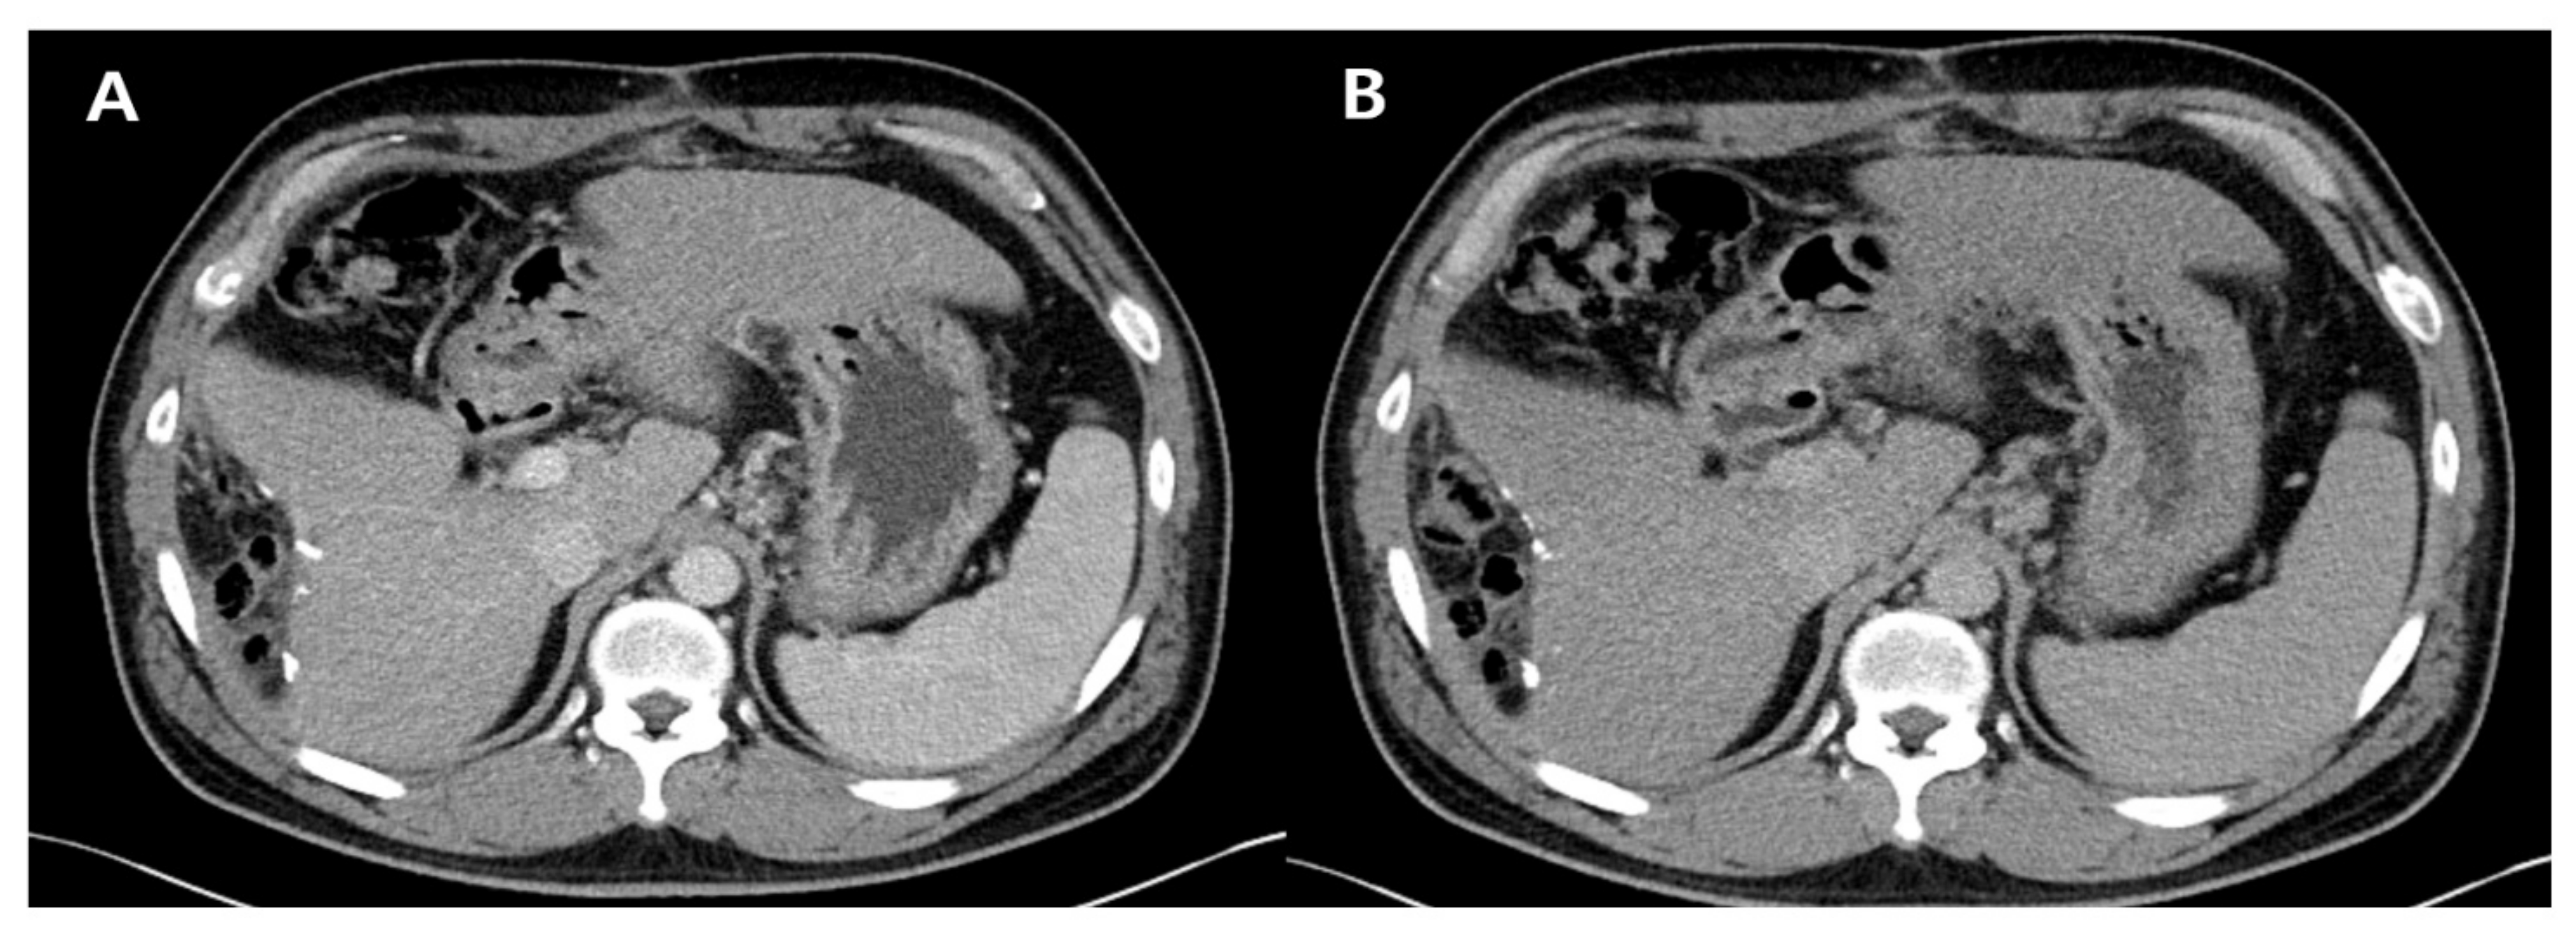

After approximately 1 year, the patient’s laboratory and radiological findings were normalized (Figure 3). His follow-up laboratory tests were as follows: AST level, 20 IU/L; ALT level, 31 IU/L; total bilirubin level, 0.63 mg/dL; albumin level, 3.56 g/dL; platelet count, 127 × 103/μL; PT, 11.2 s; and AFP level, 5.1 ng/mL. The repeat HBV DNA was undetectable.

Figure 3.

Follow-up dynamic computed tomography scan after 1 year. Multiple surgical clips at the previously resected margin are seen without new lesions: arterial phase (A) and delayed phase (B).